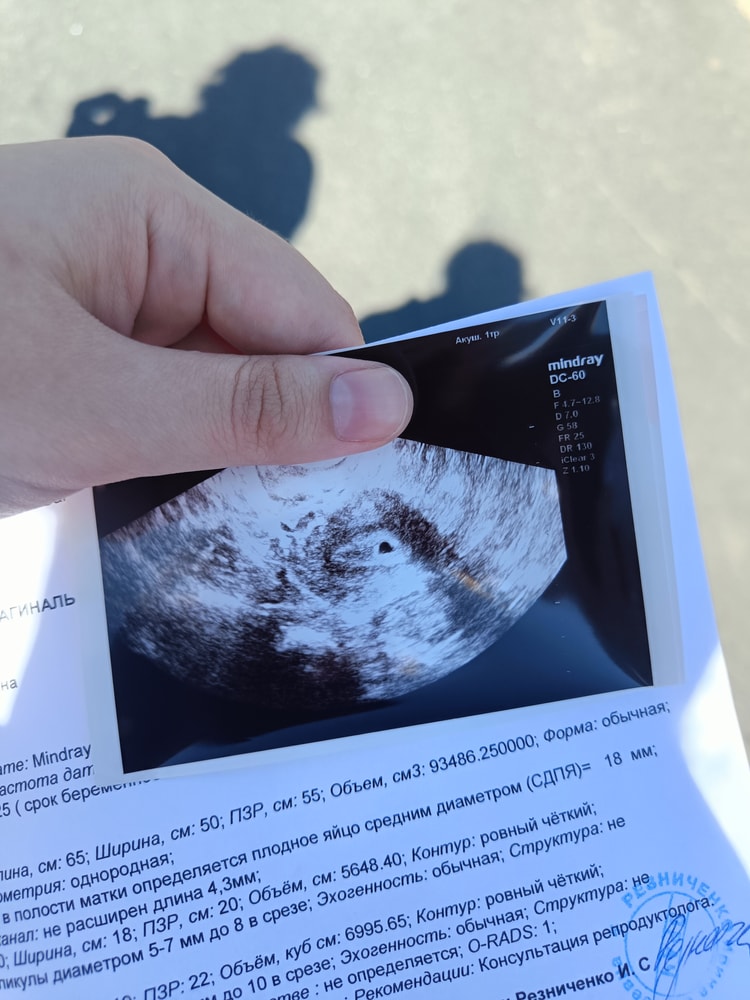

15 дпп, УЗИ.

Нужен совет знатоков, по поводу УЗИ. Сразу хочу сказать, что УЗИ я делала не по своему желанию, а по просьбе ге, чтобы подтвердить маточную беременность (после ХГЧ 1500).

УЗИ подтвердило маточную беременность. Я счастливая вышла от врача. Это мое первое в жизни беременное УЗИ и я не знала, на что надо обращать внимание. Доктор сказала - смотрим маточную, ну я и переживала только о том маточная или нет.

Получив результаты и поздравления врача, я решила посмотреть что значит ПЯ=18 мм и узнала, что оказывается, при таком ПЯ уже должен быть ЖМ (врач ничего про него не написала, но я как будто вижу его на снимках).

Хочется узнать ваш опыт, начиталась про анэмбрионовую беременность и теперь очень переживаю. Следующее УЗИ запланировано на 11 июля.

Около пя нет даже точек, с помощью которых замеряют расстояние на узи. Вам не измеряли пя, размер написали на глаз от балды.

Но замер пя все равно большеват, могла в протоколе не все цифры внести врач верно.

На 18дпп пя было 5мм и это норма, у вас не корректный замер скорее всего эмбрион находят день на 23-28дпп в зависимости от роста хгч. Расслабьтесь и ждите на след узи эмбрион.

Вам многие девочки скажут , что рано паниковать о том что вы «не видите или видите» 15 дпп действительно рано еще ставить свою Б под сомнение, ну и как я тоже вижу, там действительно проклевывается малышок 🤭☺️🤞 как раз через неделю и увидите

Анна , девочки уже глаз тут наметан ,думаю как они и говорят,замером ступили а то что там виднееца видно сразу 🤞💐

Поэтому так рано нечего идти на узи, переживать начинаете и сравнивать с другими. В пя у вас слева что-то клюется, либо жм, либо эмбрион

У вас на 15 дпп , пя 18, а у меня на 17дпп было всего пя 5,5 и жм 2,0 . А на 27 дпп, пя 21 , жм 3 . Может у вас срок не верный или пя размер не верный написали . Слишком большое для 15дпп .

Я склоняюсь к тому, что вам неправильно посчитали СВД.